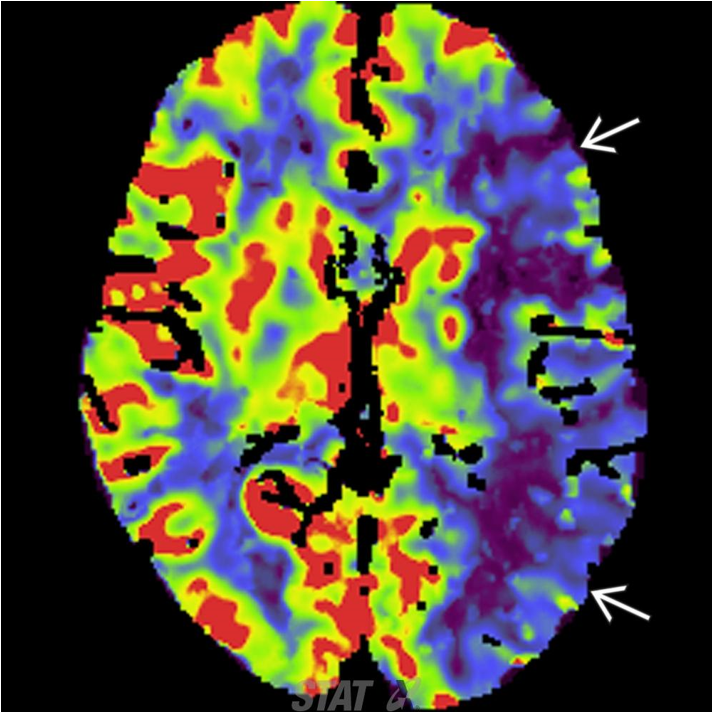

4.1.3. CT tưới máu não (CTP)

Cho thấy thay đổi các thông số tưới máu não, đánh giá “lõi” tổn thương nhồi máu và vùng tranh tối-tranh sáng.